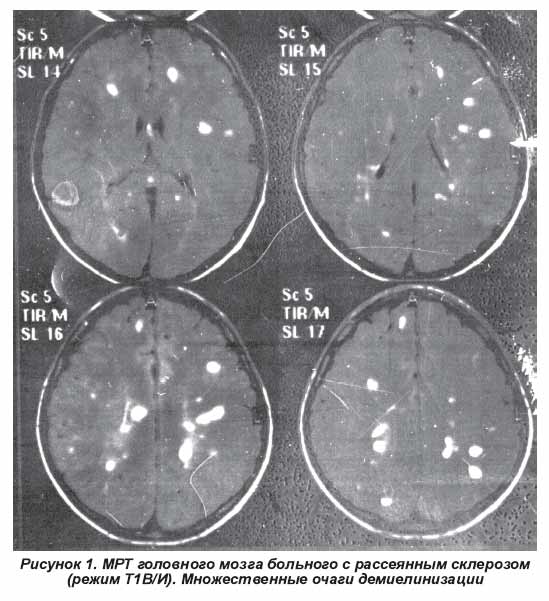

Демиелинизирующие заболевания мозга: МРТ изображения